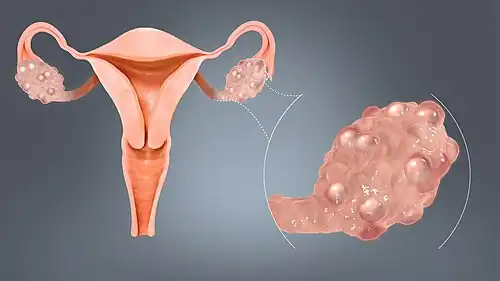

| A polycystic ovary | |

Polycystic ovary syndrome (PCOS) is the most common endocrine disorder in women of reproductive age.[13] The name originated from the observation of cysts which form on the ovaries of some women with this condition. However, this is not a universal symptom and is not the underlying cause of the disorder.[14][15]

- Polycystic ovaries: There are small cysts on one or both ovaries. Ovaries might enlarge and compress follicles surrounding the eggs. As a result, ovaries might fail to function regularly. This disease is related to the number of follicles per ovary each month, growing from the average range of 6–8 to double, triple, or more.

The syndrome acquired its most widely used name due to the common sign on ultrasound examination of multiple (poly) ovarian cysts. These "cysts" are immature ovarian follicles. The follicles have developed from primordial follicles, but this development has stopped ("arrested") at an early stage, due to the disturbed ovarian function. The follicles may be oriented along the ovarian periphery, appearing as a 'string of pearls' on ultrasound examination.[63]

Gynecologic ultrasonography first looks for small ovarian follicles.[75] To count as polycystic ovaries, at least 20 follicles need to be present, smaller than 9 mm. This used to be 12 in older diagnostic criteria.[16] A less clear marker of PCOS is enlarged ovaries.[75] Ovary need to be at least 10 cm3 to count.[16] For sexually active individuals or those that agree, a transvaginal ultrasound approach is preferred. Alternatively, AMH levels can be tested in the blood.[75] Laparoscopic examination may reveal a thickened, smooth, pearl-white outer surface of the ovary. This would usually be an incidental finding if laparoscopy were performed for some other reason, as it would not be routine to examine the ovaries in this way to confirm a diagnosis of PCOS.[78]

Most common names for this disease derive from a typical finding on medical images, called a polycystic ovary. A polycystic ovary has an abnormally large number of developing eggs visible near its surface, looking like many small cysts.[68] The name implies that PCOS is a gynecological condition only, rather than a metabolic and endocrine condition. A majority of clinicians and people with PCOS are in favour of renaming the condition, and, as of 2025, a survey is underway to find a new name.[121]